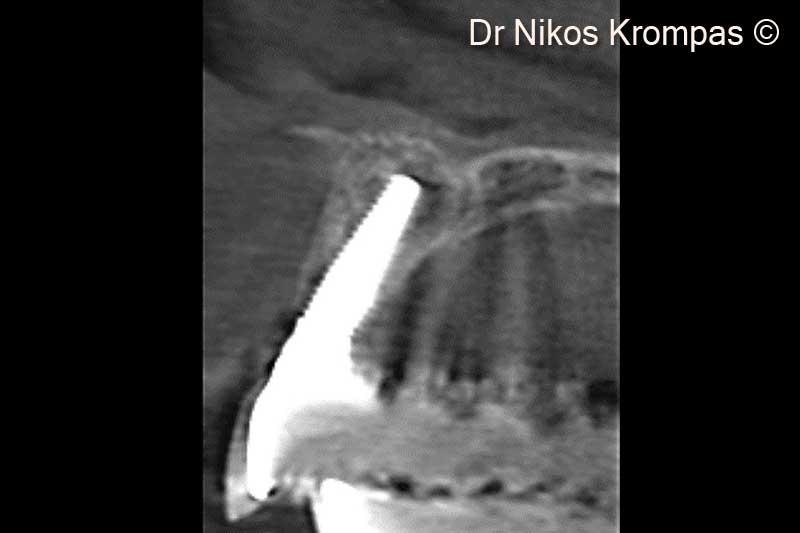

15. Cross section 2 years post-op. Note the adequate buccal plate thickness